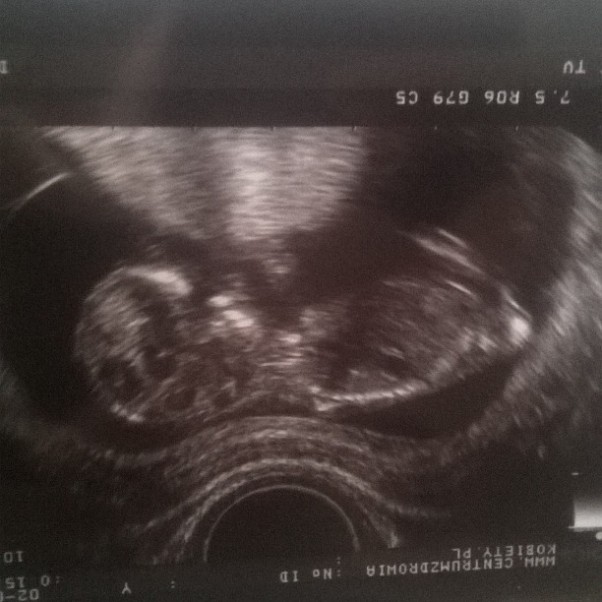

mały szkrab , który się chował i nie chciał zdradzić kim jest ale jakoś pokazał sie mamusi i tatusiowi :) tatus szczęśliwy jak mamusia że jest nasz ukochany synek ;*